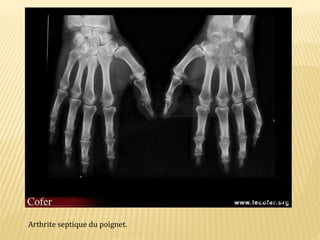

Arthrite septique du poignet.

EN FAVEUR D’UNELÉSION SEPTIQUE Articulaire périphérique: • Les signes osseux sont absents au début. • Tuméfaction des parties molles adjacentes. • puis une déminéralisation épiphysaire • pincement globale de l’interligne articulaire • érosions marginales et centrales mal définies • ostéolyse des épiphyses • et enfin, ankylose fibreuse ou osseuse séquellaire